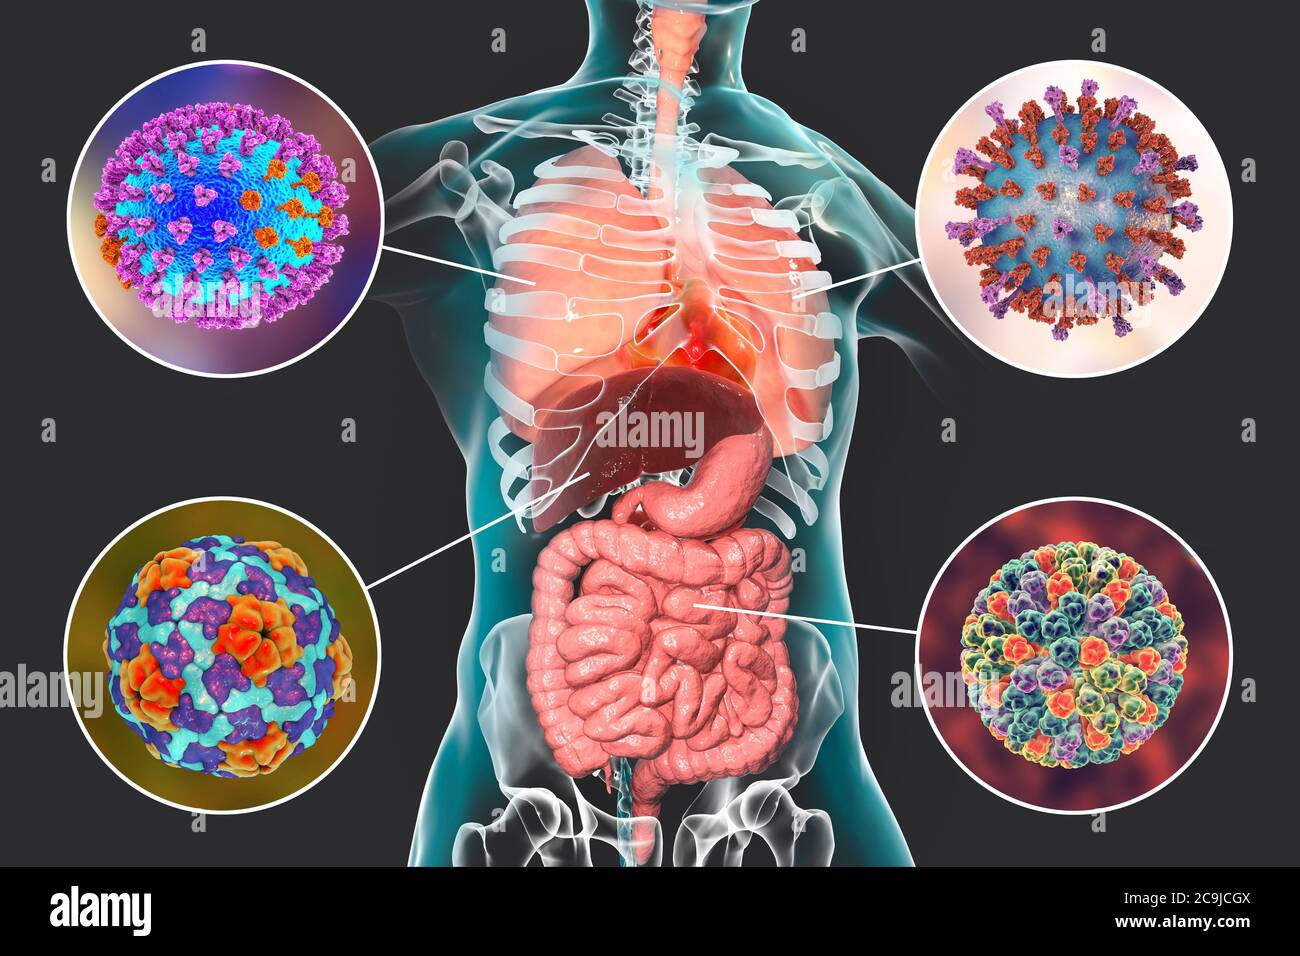

Revue générale des infections virales respiratoires – L’étiologie, la physiopathologie, les symptômes, les signes, les diagnostics et les pronostics à partir des Manuels MSD,.

De nombreux agents pathogènes peuvent provoquer des infections des voies respiratoires. Bon nombre de ces infections produisent des signes et des symptômes similaires, mais.

Selon l'Organisation mondiale de la santé, les infections des voies respiratoires telles que la tuberculose, la grippe et la pneumonie ont été responsables de plus de 4 millions de.